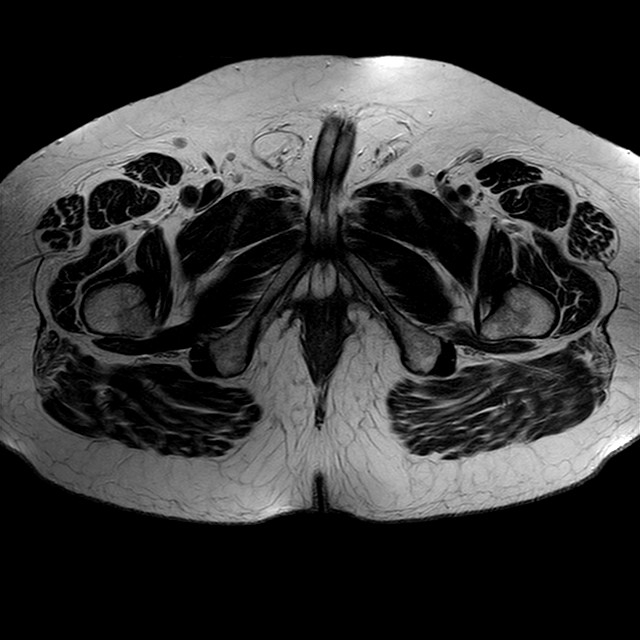

Esami: RMN BACINO

eT2w TSE

Evidenti e simmetriche alterazioni osteofitosiche in regione coxo femorale con riduzione delle rime articolari. Degenerazione completa del cercine glenoideo. Non attuali segni di versamento articolare. Non segni di edema osseo che escludono attuale algodistrofia od osteonecrosi. Lieve e simmetrica riduzione del trofismo della muscolatura glutea.